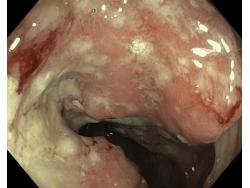

Nowotwory przewodu pokarmowego